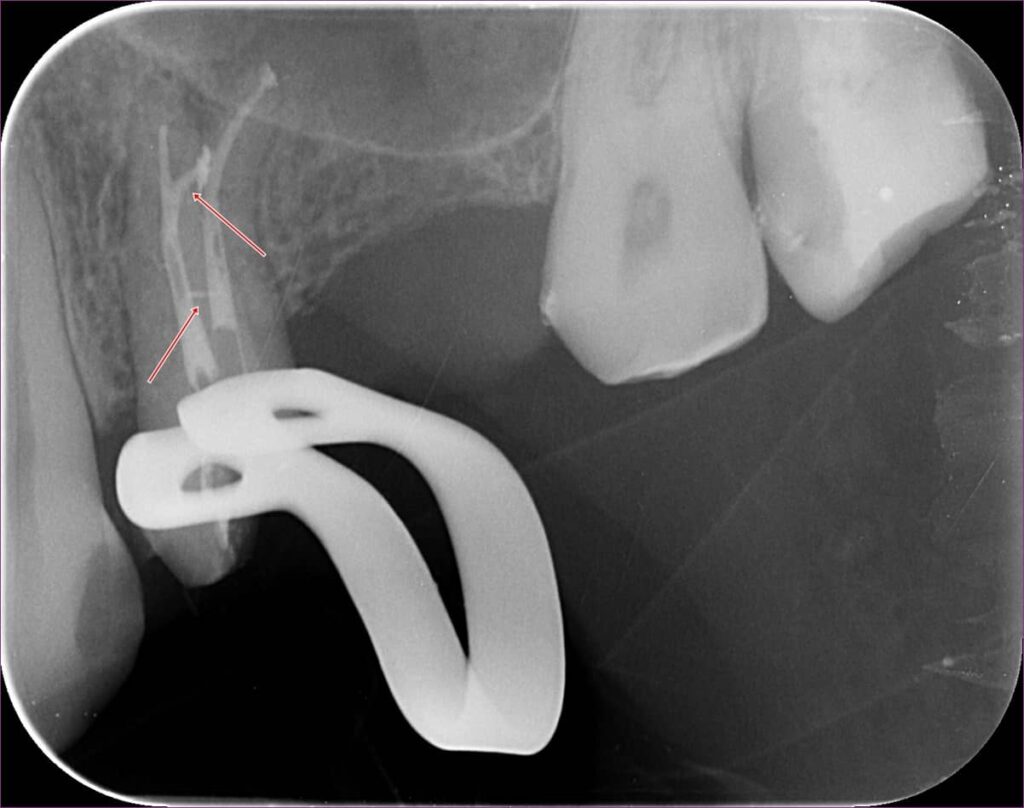

Mint minden alkalommal, a gyökértömés megkezdése előtt a fog csatornarendszerét többféle vegyszerrel, illetve egy speciális átöblítő rendszerrel kezeltük, hogy a benne lévő idegszövet-maradványokat teljes mértékben el tudjuk távolítani. Erre azért van szükség, mert az úgynevezett oldalcsatornákat mechanikusan, gyökérkezelő tűkkel nem tudjuk közvetlenül elérni. A gyökértömésről készült felvételen nagyszerűen látszik egy ilyen oldalcsatorna teljes feltelítődése: ezt nyilakkal jelöltük.